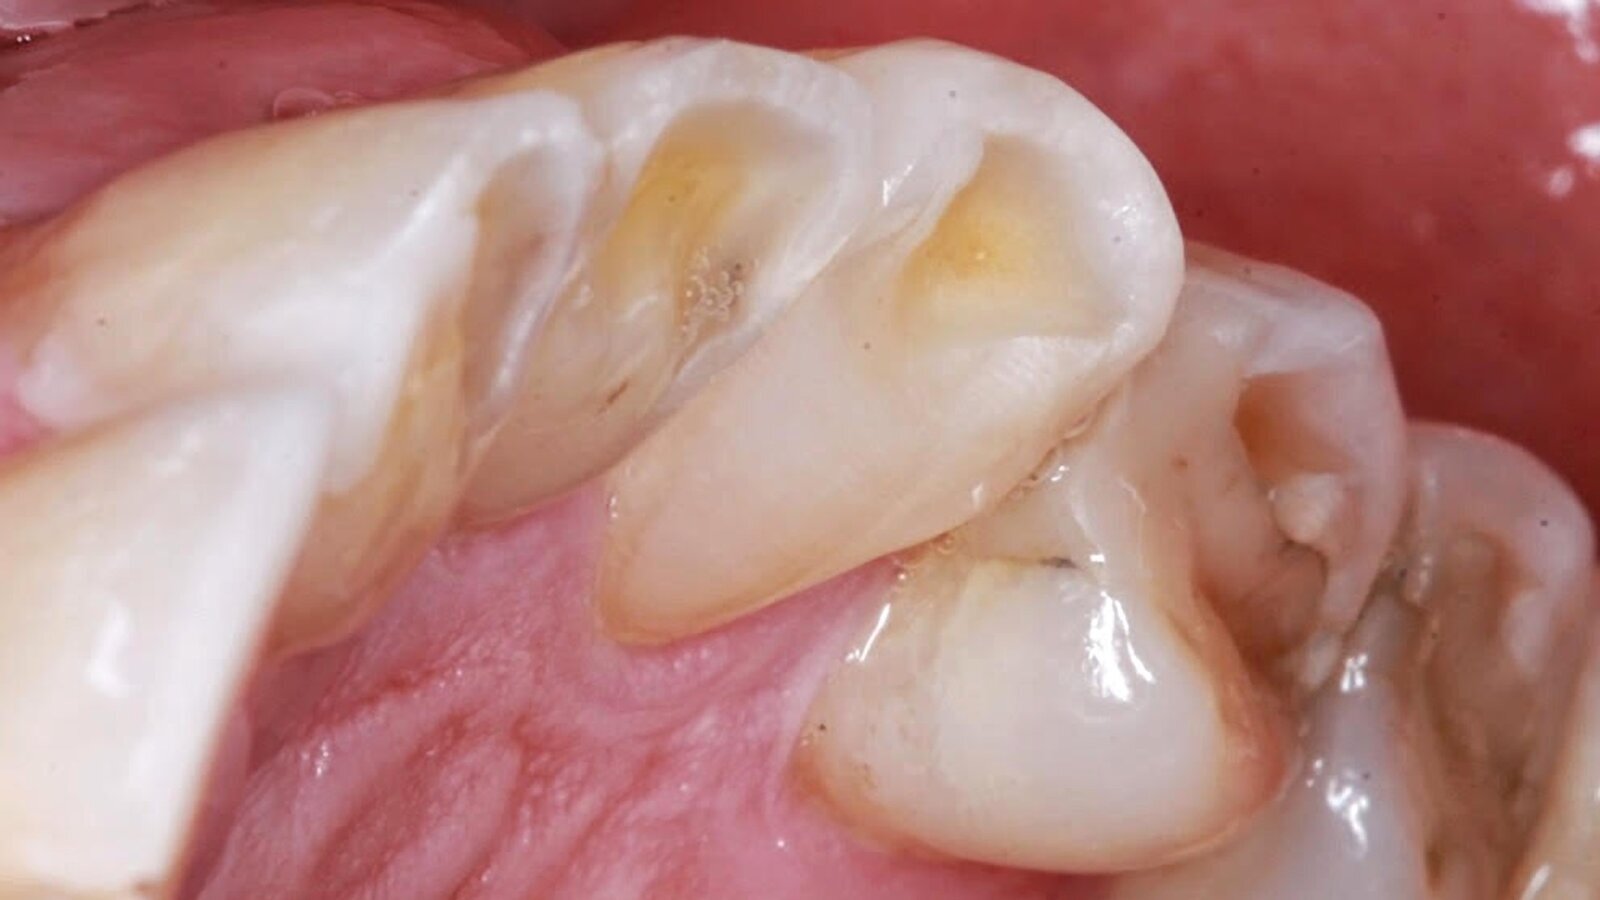

La imagen muestra claramente el desgaste dental causado por el apretamiento dentario, que es el principal síntima del bruxismo (Foto: Carlos Ripoll)

Generalmente, el paciente que padece bruxismo presenta un desgaste en la superficie de los dientes y retraimiento de las encías, hasta el punto de que el cuello de los dientes queda expuesto, produciendo hipersensibilidad dental. De hecho, el odontólogo debería saber detectar el bruxismo en un paciente por el estado de sus encías.